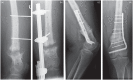

Nonunions are a relevant economic burden affecting about 1.9% of all fractures. Rather than specifying a certain time frame, a nonunion is better defined as a fracture that will not heal without further intervention.Successful fracture healing depends on local biology, biomechanics and a variety of systemic factors. All components can principally be decisive and determine the classification of atrophic, oligotrophic or hypertrophic nonunions. Treatment prioritizes mechanics before biology.The degree of motion between fracture parts is the key for healing and is described by strain theory. If the change of length at a given load is > 10%, fibrous tissue and not bone is formed. Therefore, simple fractures require absolute and complex fractures relative stability.The main characteristics of a nonunion are pain while weight bearing, and persistent fracture lines on X-ray.Treatment concepts such as 'mechanobiology' or the 'diamond concept' determine the applied osteosynthesis considering soft tissue, local biology and stability. Fine wire circular external fixation is considered the only form of true biologic fixation due to its ability to eliminate parasitic motions while maintaining load-dependent axial stiffness. Nailing provides intramedullary stability and biology via reaming. Plates are successful when complex fractures turn into simple nonunions demanding absolute stability. Despite available alternatives, autograft is the gold standard for providing osteoinductive and osteoconductive stimuli.The infected nonunion remains a challenge. Bacteria, especially staphylococcus species, have developed mechanisms to survive such as biofilm formation, inactive forms and internalization. Therefore, radical debridement and specific antibiotics are necessary prior to reconstruction. Cite this article: EFORT Open Rev 2020;5:46-57. DOI: 10.1302/2058-5241.5.190037.